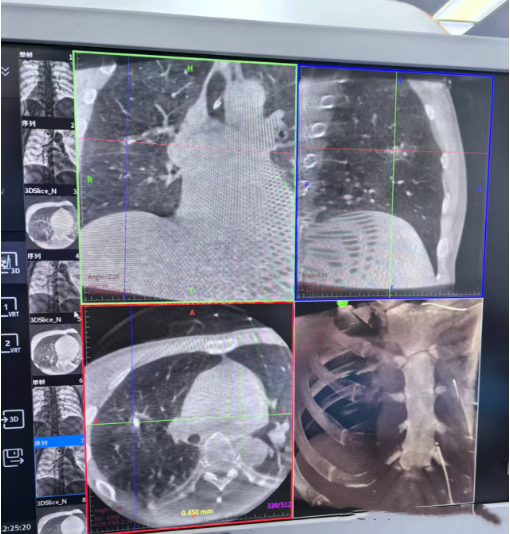

消融术后

3. 尖端冷冻探针经支气管抵达:在导航与实时影像双重保障下,超细冷冻探针经由自然腔道(支气管)直达肺外周结节。探针尖端释放的极低温(可达-140℃以下)可在瞬间“冰封”癌细胞,摧毁肿瘤组织,而对周围健康肺组织损伤极小,真正实现“无痕”物理消融。